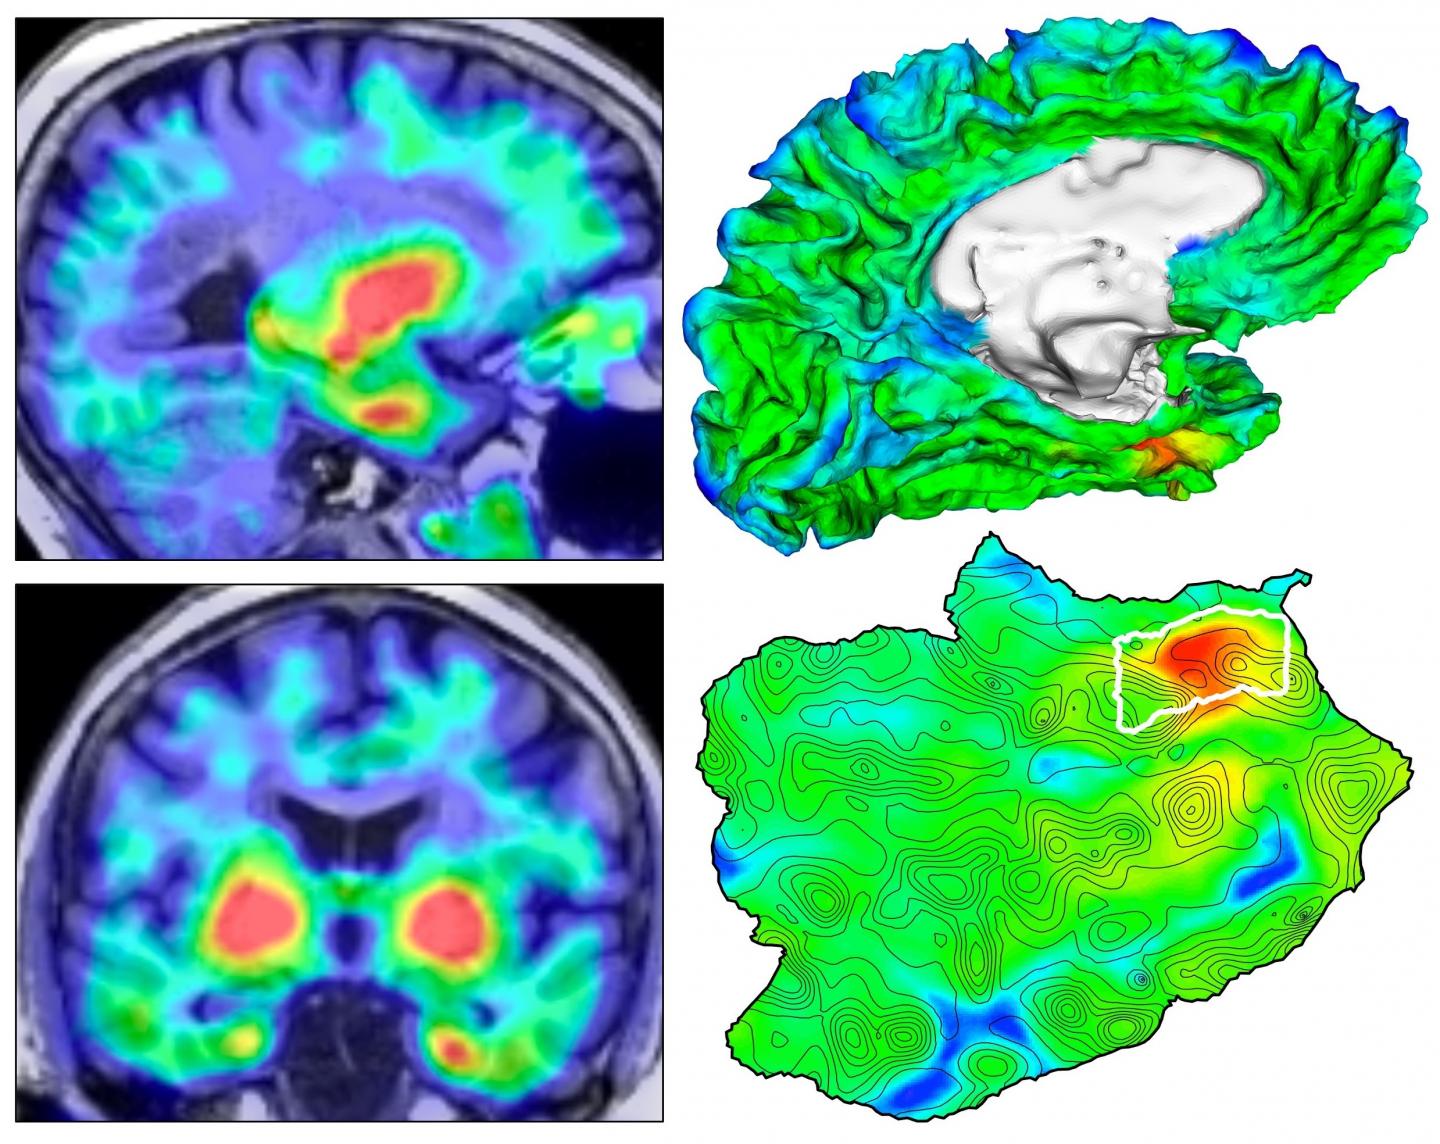

Learn the warning signs of dementia. Researchers Pinpoint Brain Region As Ground Zero Of Alzheimer S Disease Usc News

With an alzheimer's disease diagnosis, the questions will probably follow as you struggle to come to terms with this disease. Alzheimer S Disease Brain Map Charts Thousands Of Protein Changes

Alzheimer S Disease Brain Map Charts Thousands Of Protein Changes from www.genengnews.com